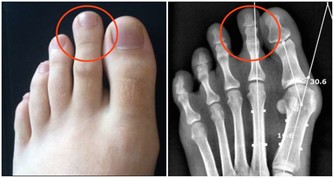

1、頭部根據反射療法,腳趾尖的部分直接連接到頭部和大腦。

所以透過按摩可以幫助緩解頭痛,而且對大腦的健康很有幫助。